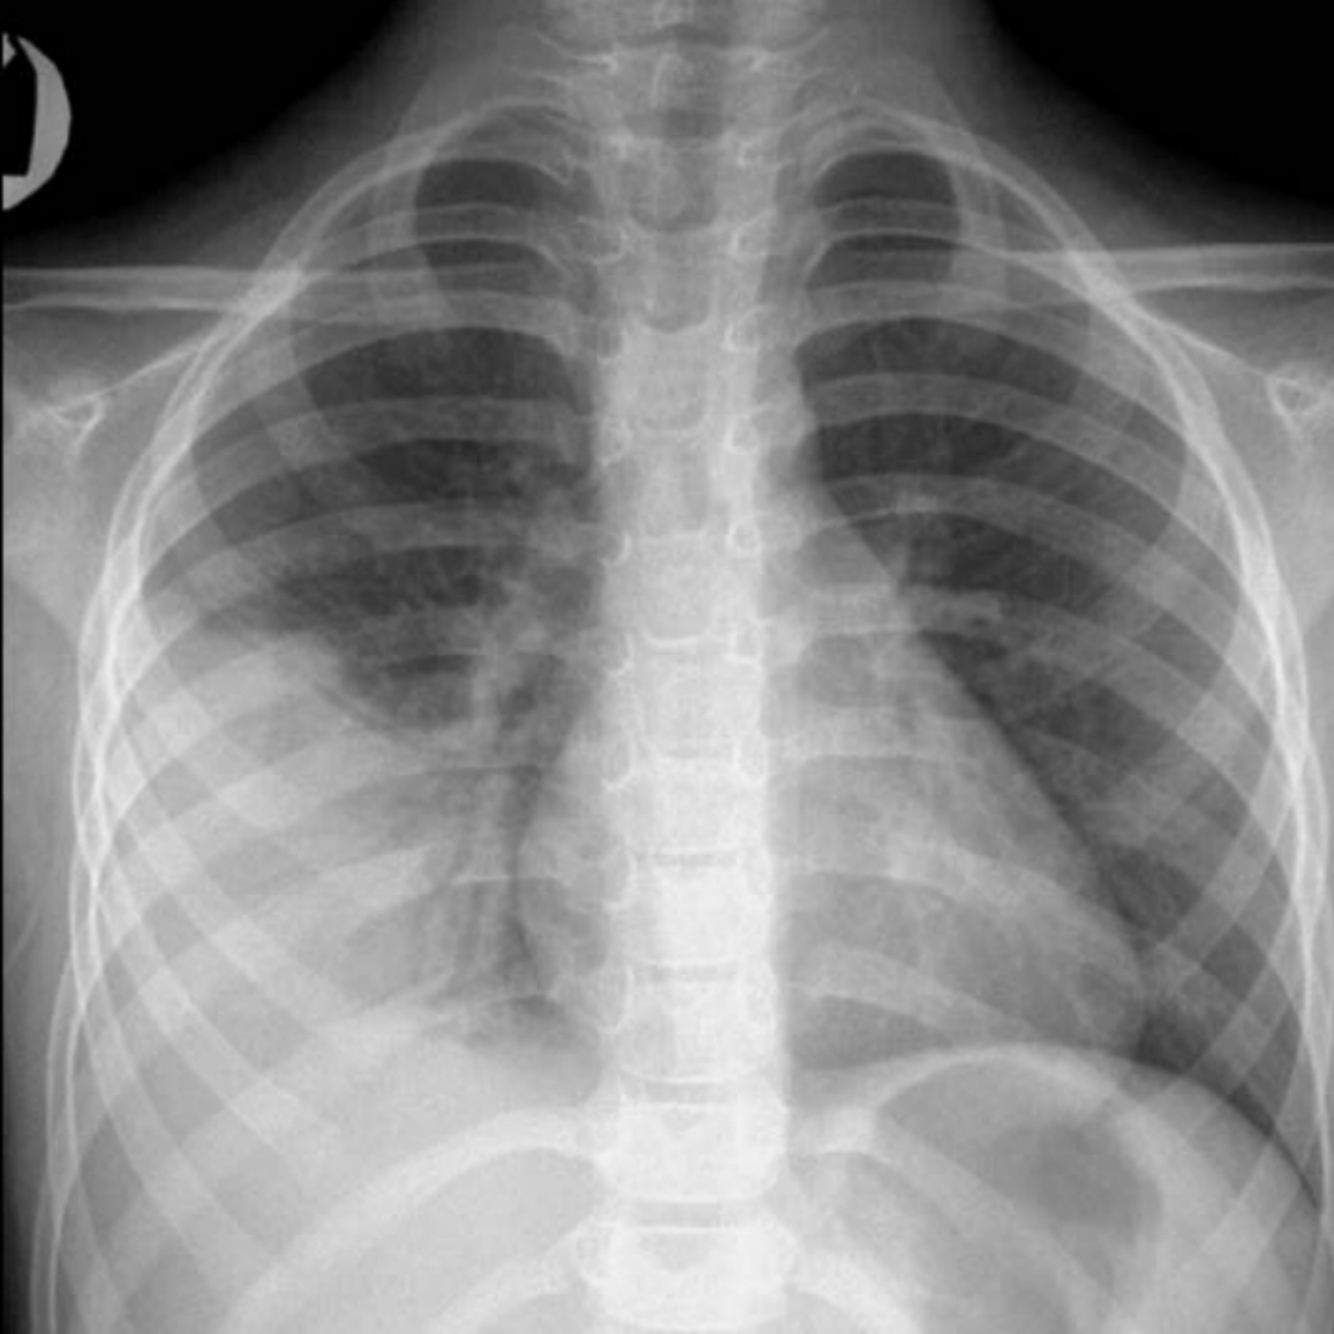

CXR: Frontal chest radiograph shows right lower lobe consolidation and the silhouette sign—the adjacent diaphragm is obscured, the right cardiac silhouette, anterior to the consolidation, is preserved.

Diagnosis: Right lower lobe pneumonia.